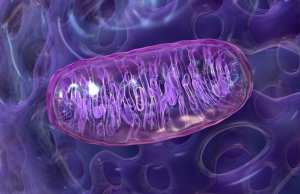

Cells contain biological engines called mitochondria that convert food into energy the body can use. Mitochondria utilize a complex system of vitamins, minerals, essential lipids,... Continue reading